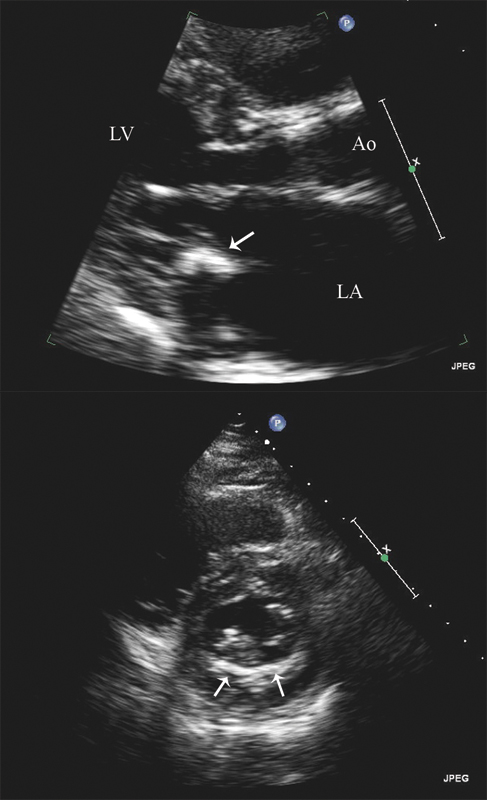

فحوصات تشخيصية لبعض امراض القلب والشرايين التاجية